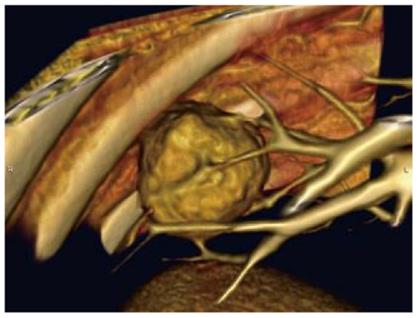

先进的CT技术“重建”出肺癌肿块的细微特征